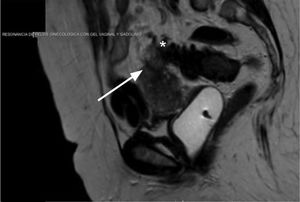

Se realizó enema opaco con doble contraste que mostró como único hallazgo patológico formaciones diverticulares sin signos de complicación y una resonancia magnética que identificó una fístula entre el colon sigmoide y el útero con características inflamatorias (fig. 1).

El enema opaco no mostró la comunicación entre ambos órganos como sucede habitualmente7. Si bien la tomografía computarizada es muy sensible y específica para el diagnóstico de las complicaciones agudas de la diverticulosis, la identificación del trayecto fistuloso y la exclusión diagnóstica de una neoplasia es difícil. Por ello utilizamos la resonancia magnética que tiene mayor precisión para el diagnóstico de la fístula además de permitir determinar sus características inflamatorias8.